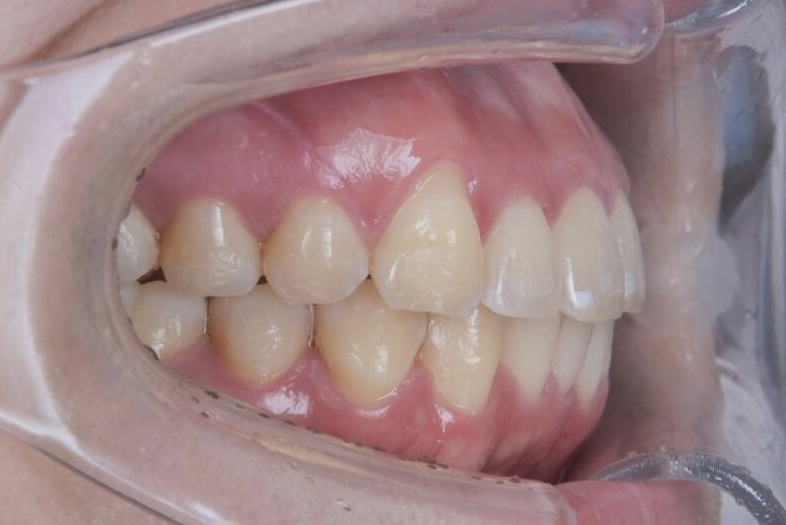

診断の結果、上顎前歯の唇側傾斜が強く、歯並びの状態だけを見ると抜歯を検討するケースでしたが、患者さまの「できるだけ抜歯は避けたい」というご希望を踏まえ、奥歯の遠心移動とIPR(歯と歯の間をわずかに調整する処置)を適切に組み合わせることで、抜歯を行わずに治療を進めました。

治療期間は1年10ヶ月、通院は2〜3ヶ月に1回と無理のないペースで進め、治療の経過を確認しながら計画的に歯並びと咬み合わせを整えました。

その結果、前歯の突出感や下の前歯のガタつきが改善し、前歯でしっかり噛める機能的な咬み合わせを獲得することができ、見た目と機能の両面で良好な結果が得られた症例です。

AFTER